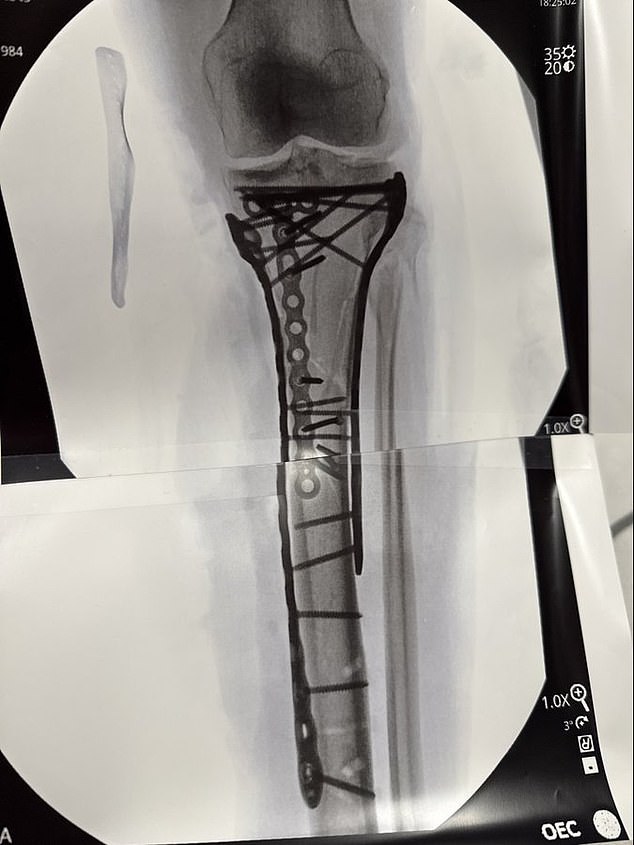

The 41-year-old revealed how close she came to amputation – with her leg now supported by dozens of metal pins

Vonn joked last week that she was ‘bionic for real now’ after sharing an x-ray of her leg, which is now held together by dozens of metal pins.